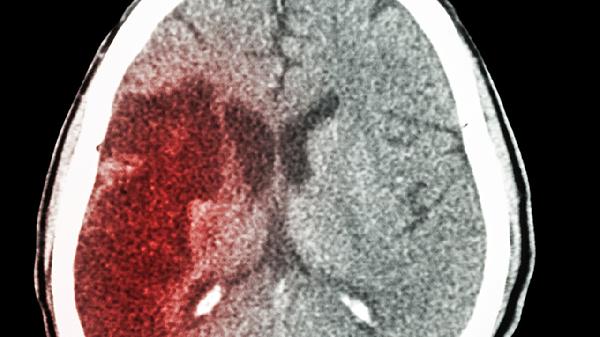

但需注意,严重神经系统疾病如阿尔茨海默病、血管性痴呆等器质性病变,单纯使用益智康脑丸效果有限。部分患者可能因个体差异或病因复杂,用药后症状改善不明显。此外,中药起效相对缓慢,通常需要较长时间规律服用才能评估效果。